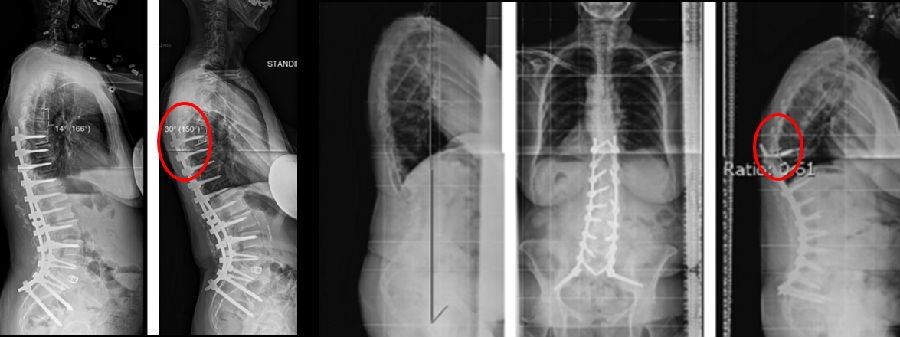

图17 据文献报道,腰椎前凸(LL)过度矫正和SVA基线位置不当,均为增加PJK发生的风险因素

Ø 术后PI-LL不匹配,PI-LL大于10°

图21 术后PI-LL不匹配,大于10°